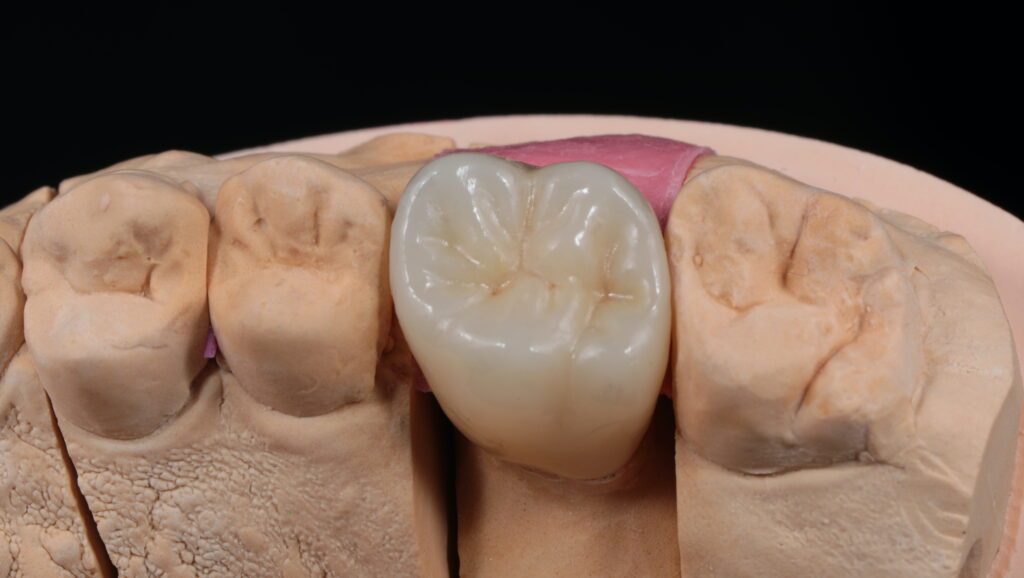

歯科治療では、病変部や欠損部を詰め物、被せもの、義歯、インプラントなどで修復することが最終目標です。この重要な最終段階を決定するのが補綴専門医の役割です。美しく、再治療の必要がない完璧な治療をご提供します。

全顎治療(フルマウス治療)では、歯の健康だけではなく、見た目の美しさも重視しております。